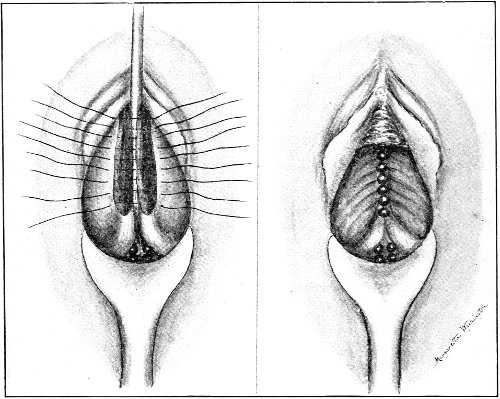

An accurate knowledge of the anatomy and mechanism of the female perineum is essential to an understanding of the nature and treatment of injuries to this structure. The anatomical structures lying between the anus behind and the symphysis pubis in front are those that most directly interest the gynecologist. Proceeding from 57 below upward, we find the following structures lying in superimposed planes: the skin, the superficial fascia, the deep layer of the superficial fascia, the transversus perinæi and the sphincter vaginæ muscles, the anterior layer of the triangular ligament, the posterior layer of the triangular ligament, the levator ani muscle (Fig. 19).

Fig. 18, A.—Superficial structures of the female perineum (Weisse).

Fig. 19.—Dissection of female perineum: on the left side the perineal muscles are exposed by the reflection of the perineal fascia; on the right side the muscles and the superficial layer of the triangular ligament have been removed, thereby exposing the deep layer of the ligament. S. V., Sphincter vaginæ muscle.

The vagina passes through these structures. They surround and support the ostium vaginæ as the fascia and muscles surround and support the opening of the rectum or the anus. The muscles and fasciæ are attached in the median line between the anus and the vagina, and therefore this part of the body, which is called the perineum, is supported or maintained in its 58 proper position by these various structures. The transversus perinæi arises from the ramus of the ischium and is inserted in the perineum. The bulbo-cavernosus, or sphincter vaginæ, arises in the perineum and is inserted in and about the clitoris. The inner fibers of the levator ani arise from the symphysis pubis and are inserted in the perineum and the lower part of the vagina (Fig. 20). When these muscles contract, their action, therefore, is to draw the perineum upward and forward. At the same time the anus is drawn upward and forward, and so also is the posterior margin of the ostium vaginæ and the lower portion of the posterior vaginal wall.

Fig. 20.—Dissection of female perineum, showing the deeper structures after removal of the levator and sphincter ani muscles.

The vagina has no circular sphincter like the anus, but 59 the vaginal month is kept closed by the action of the transversus perinæi, sphincter vaginæ, and levator ani muscles, which draw the perineum forward, and thus keep the posterior vaginal wall in apposition with the anterior wall.

Fig. 21.—Muscular floor of the pelvis seen from above.

This sling of muscles and fascia, which surrounds and supports the opening of the vagina, may readily be felt in the nulliparous woman by introducing the finger in the vagina and pressing backward and outward toward the ischio-rectal fossa. We then feel plainly, immediately within the ostium vaginæ, a firm resisting band of tissue, apparently about half an inch broad, embracing the posterior portion of the lower vagina. This band is formed by the inner edges of the various muscles and planes of fascia that have been described.

Fig. 22.—Sagittal section showing relations of the several layers of fascia within the pelvic floor (Dickinson).

The vagina extends, as a transverse slit in the pelvic floor, upward and backward, approximately in the direction 60 of a line drawn from the ostium vaginæ to the fifth sacral vertebra. It is approximately parallel with the conjugate of the brim, so that when the woman is erect the long axis of the vagina is inclined at an angle of 60° to the horizon. The vagina is not a vertical open tube: it is a slit in the pelvic floor, in health always closed by the accurate apposition of the anterior and posterior walls (Fig. 21). The anterior vaginal wall is about 2½ inches long in a vertical mesial line. The posterior vaginal wall is about 3½ inches long. The vaginal walls are triangular in shape, being broader above than below. The shape of the normal vagina at the pelvic outlet is shown by Fig. 23. The section here shows the vaginal 61 slit of the shape of the letter H. The portions of the slit extending backward and somewhat outward are called the vaginal sulci or furrows. They are directions of diminished resistance in which tears are liable to occur.

Fig. 23.—Section illustrating the characteristic form of the vaginal cleft (Henle): Ua, urethra; Va, vagina; L, levator ani; R, rectum.] 62